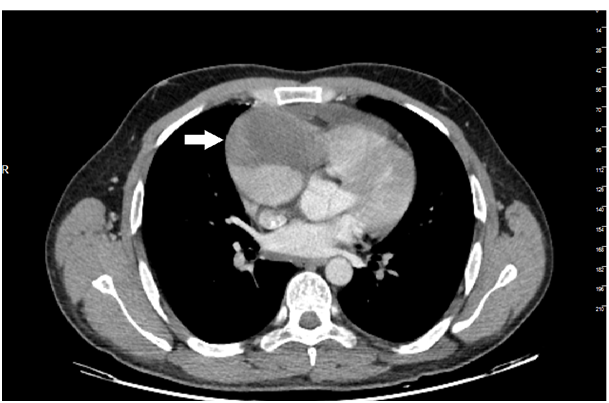

27years old male patient admitted to our outpatient clinic with progressive, pleuritic chestpain unrelated to exertion for a month with no significant medical history. The patient was diagnosed with acute pericarditis at an center and receiving ibuprofen and colchium treatment for three weeks. There was no pathological finding on cardiacaus cultation, blood pressure was 110/80mmHg, heart rate was 110bpm. Electrocardiography showed sinustachicardia and minimal ST segment elevation in all leads. There was a slight cardiomegaly in chest X-ray (Figure 1). Cardiac markers and inflammatory marker were elevated; troponin-I 1112ng/L (0-100), CK748 U/L (0-190), CK-MB 95 U/L(3-25), ESR 65, CRP 75 was detected. Transthorasic echocardiography revealed a 45x60 mm of cavitary mass compressing the right atrial free wall along with pericardial effusion (Figure 2); which was the only location of pericardial effusion in his previous examination a month ago. The patient was admitted to CCU. An aneursym 100x70x60mm in diameter, originating from right coronary artery extending to right atriallateral wall border and compressing externally, which contains thrombus material in its cavity was detected in cardiac computed tomography (CT) (Figure 3). Coronary angiography revealed a giant aneurysm communicated with RCA (Figure 4) without any abnormalty on left coronary arteries. The patient was given to emergency surgery because of the risk of pericardial tamponade. Aneurysmectomy was done and the remained cavity was closed primarily. Pathological examination was reported as polymorpho nuclear leukocyte and mononuclear inflammatory cell infiltration without elastic fibers and a pseudoaneursym of the coronary artery. The patient was discharged without any complication.

Figure 4 Giant right coronary artery aneurysm in coronary angiography (Black arrow).